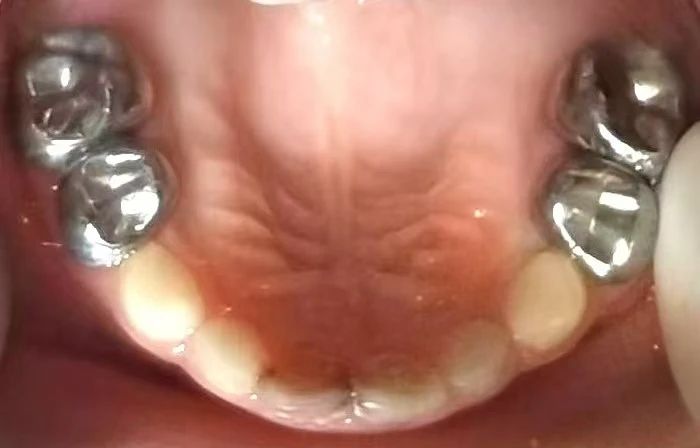

乳牙預(yù)成冠一種是預(yù)先成型的,與牙齒非常貼合的不銹鋼金屬牙冠,適用于后牙。另一種是透明的預(yù)成冠,適用于前牙。內(nèi)部中空以容納樹脂,修復(fù)后須去除冠套。

1、大面積齲壞的蛀牙,影響兒童的咀嚼功能,需要修補(bǔ)。齲壞大于兩個牙面。如果采用傳統(tǒng)方法補(bǔ)牙容易粘不住,所以咀嚼黏硬食物時補(bǔ)牙材料可能脫落。對于這種情況,采用金屬預(yù)成冠的修補(bǔ)效果更好用。

2、容易蛀牙的兒童,加上口腔衛(wèi)生狀況維護(hù)不佳,年齡小的孩子尚未形成良好的口腔衛(wèi)生習(xí)慣,可以選擇用金屬預(yù)成冠修復(fù)乳牙缺損,比傳統(tǒng)的補(bǔ)牙更不容易再壞。

3、牙神經(jīng)壞死的牙齒,變得脆弱、容易折斷,在完成乳牙根管治療后,還需要用金屬預(yù)成冠將牙齒保護(hù)起來。

4、牙齒發(fā)育異常,如牙釉質(zhì)或牙本質(zhì)發(fā)育不全的牙齒,也可以做個金屬預(yù)成冠,幫助恢復(fù)牙齒的外形和功能。